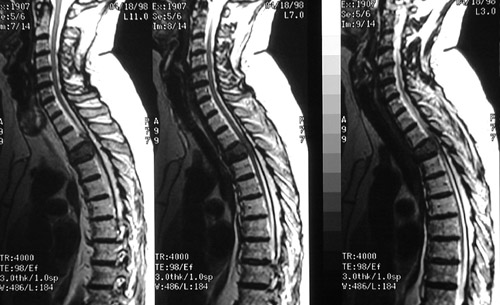

These sagittal view from an MRI scan reveal bony destruction of the T3 vertebral body in a patient with metastatic renal cell carcinoma.